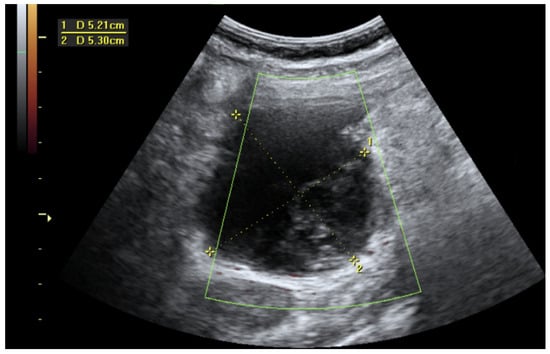

- Hung, N.K.; Ha, D.M.; Khuong, N.H.; Anh, N.N.; Linh, P.T.T.; Anh, H.M.; Hiep, D.V.; Duc, N.M. Splenic ectopic pregnancy: Rare location of ectopic pregnancy, how does it present? Radiol. Case Rep. 2023, 18, 3884–3888. [Google Scholar] [CrossRef] [PubMed]

- Python, J.L.; Wakefield, B.W.; Kondo, K.L.; Bang, T.J.; Stamm, E.R.; Hurt, K.J. Ultrasound-Guided Percutaneous Management of Splenic Ectopic Pregnancy. J. Minim. Invasive Gynecol. 2016, 23, 997–1002. [Google Scholar] [CrossRef] [PubMed]